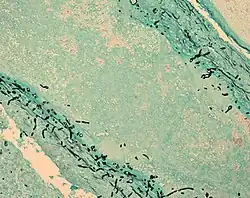

| Fungus (black) in brain tissue | |

Fungal meningitis refers to meningitis caused by a fungal infection.